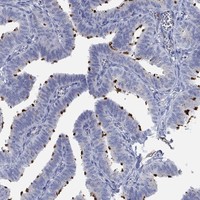

Immunohistochemical staining of human fallopian tube shows strong cilia positivity in glandular cells.